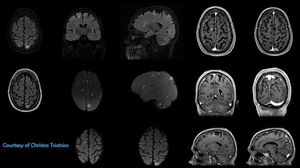

Figure shows a patient with multiple brain metastases. High resolution MR imaging based on 3D T2 FLAIR with fat-suppression, 3D T1 FSPGR, 2D axial FLAIR and axial DWI (b0, b500, b1000). Moreover, 3D MIPs of the volumetric T2 FLAIR, for segmentation and volumetric calculation of the metastatic lesions, are shown.